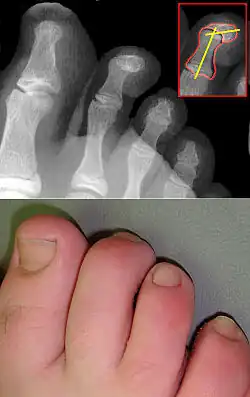

Молоткообразная деформация пальцев стопы (молоткообразные пальцы) — это наиболее распространённая деформация второго, третьего и четвертого пальцев стопы. Проявляется из-за сгибательной контрактуры проксимального межфалангового сустава, переразгибания плюснефалангового и дистального межфалангового суставов. В результате чего пальцы приобретают форму молоточка. Молоткообразная деформация пальцев стопы — это следствие сложной общей деформации стопы. Данная деформация возникает вследствие нарушения натяжения сухожилий мышц-сгибателей, а также из-за снижения подвижности межфаланговых суставов пальцев стопы. При снижении активности пальцев суставы как бы фиксируются в согнутом состоянии.[1]

Очень часто молоткообразная деформация пальцев сопровождается такими ортопедическими патологиями как: вальгусная деформация большого пальца, поперечное плоскостопие, церебральный паралич, полиомиелит, миелодиспластическая полая стопа и др. Данная деформация стопы опасна таким осложнением, как развитие отстеоартроза вследствие подвывиха фаланг пальцев. Также при этом недуге образуются большие мозоли и натоптыши из-за сильного давления и постоянного трения обуви.